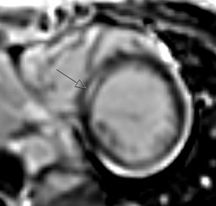

Childhood Heart Structure Problems (Congenital Heart Disease)

Description: Congenital heart diseases are heart problems that children are born with. These diseases range from simple to complex and many require surgery or other procedures.

Why MRI: Heart MRI is used to capture images in all types of congenital heart disease and at all ages. It can be used to help determine if and what type of surgery might be needed. It can also be used after surgery for routine follow up and check if there are any complications.

Heart MRI captures images of the heart and blood vessels to help see exactly the location and size of the structures. Sometimes 3D models are made to help see everything. Heart MRI can also measure flow in blood vessels and measure how well the heart muscle is pumping.

Images: ASD, 3D aorta, Flow in single ventricle